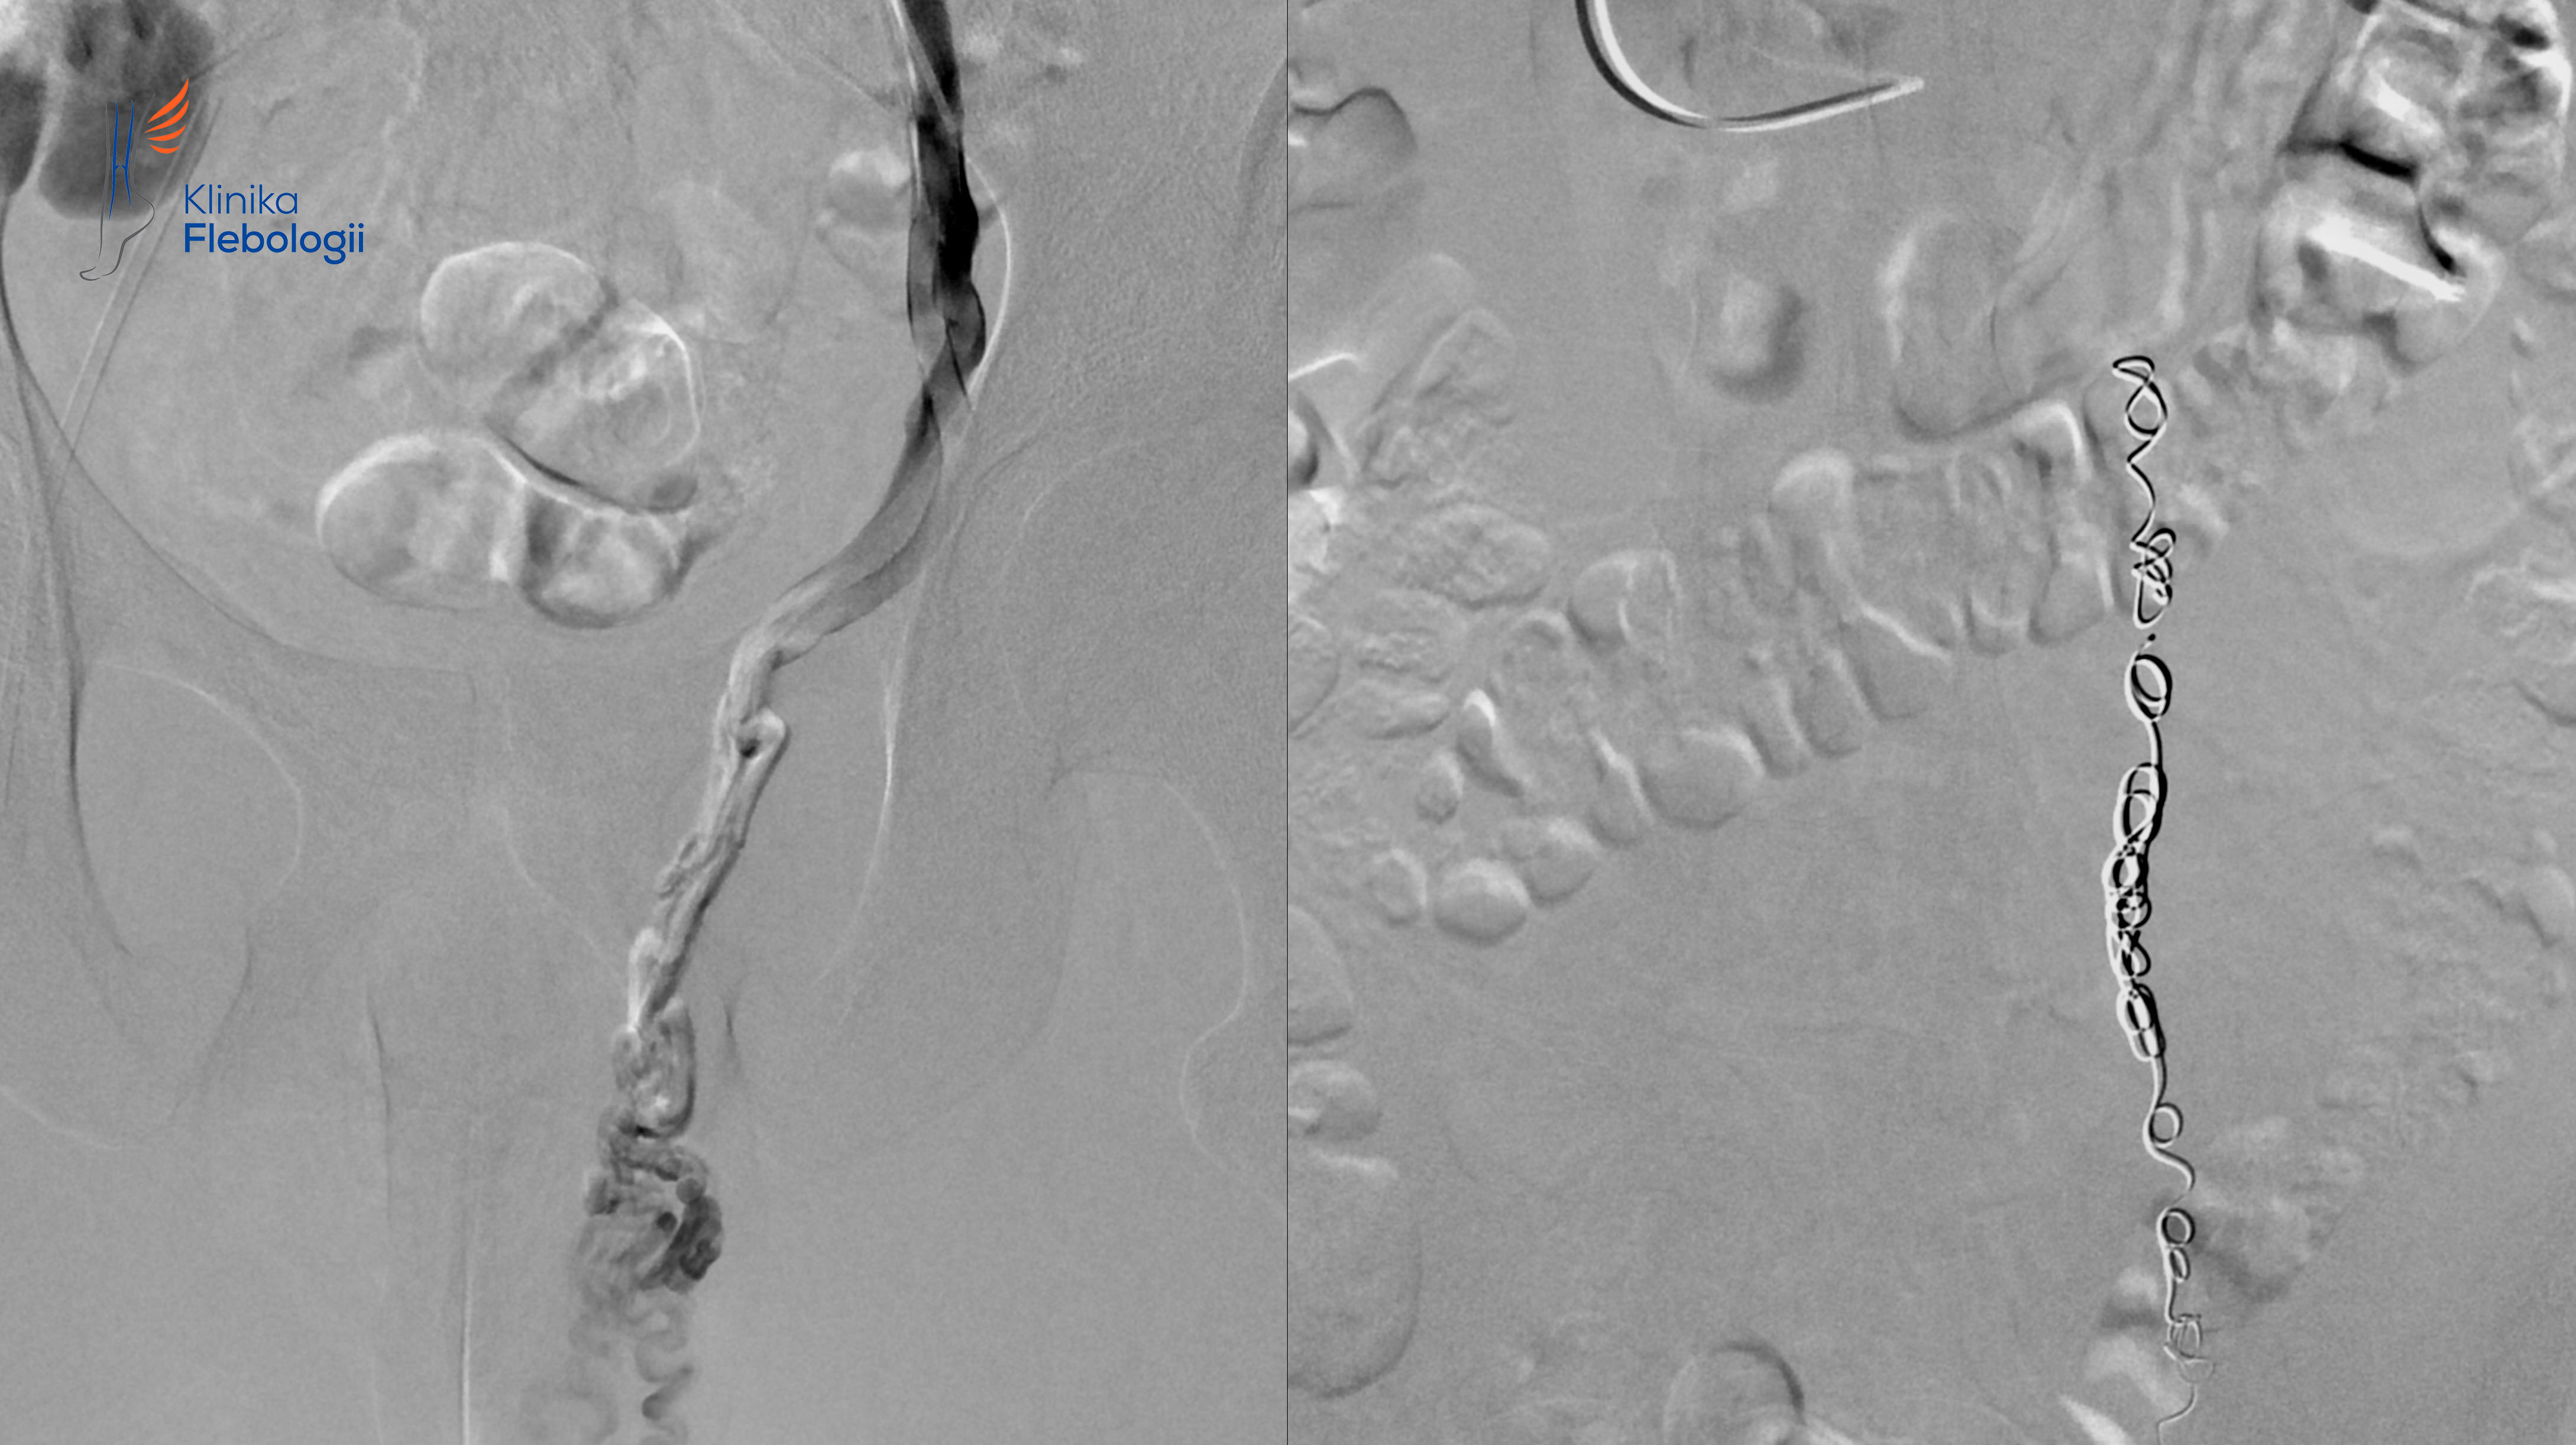

Pierwszy zabieg chirurgicznego zaopatrzenia żylaków powrózka został wykonany w roku 1952 przez Tullocha. Najnowsze podejście do leczenia tej przypadłości męskiej polega na przezskórnej embolizacji wewnątrzżylnej, czyli leczeniu przyczynowym skutkującym zamknięciem żyły jądrowej i niewydolnych naczyń żylnych splotu wiciowatego.

Jedynym sposobem przyczynowego leczenia w przypadku zespołów May-Thurnera czy zespołu dziadka do orzechów są metody wewnątrzżylne. Najbardziej skuteczne i najmniejinwazyjne ze wszystkich metod leczenia żylaków powrózka nasiennego są metody oparte na technice embolizacji wewnątrzżylnej, wykonywanej z niemalże bezbolesnego dostępu przezskórnego.

Metoda embolizacji wewnątrzżylnej pozwala w sposób wyjątkowo małoinwazyjny (niepotrzebne jest znieczulenie ogólne) i dokładny zamknąć, bez nacinania, źle działające naczynie żylne odpowiadające za refluks i tworzenie żylaków w obrębie worka mosznowego. Najczęściej zamykana jest lewa żyla jądrowa i jej odgałęzienia. Zabiegi wewnątrzżylne pozwalają wyleczyć również rzadsze przyczyny żylaków worka mosznowego, w przypadku których klasyczne podejście urologiczne jest nieskuteczne (około 20% pacjentów cierpiących na tę przypadłość).

Zabieg embolizacji wewnątrzżylnej polega na zamykaniu niewydolnych żył przy użyciu specjalnych spiral z jednoczasową sklerotyzacją lub klejeniem poszerzonych splotów żylnych. W Klinice Flebologii w Warszawie leczone są również żylne przecieki kończynowe i żylaki atypowe na nogach, które często współtowarzyszą żylakom powrózka nasiennego.

Zabiegi embolizacji żylaków powrózka nasiennego wykonywane są w pracowni hemodynamiki Szpitala Medicover w Warszawie. Wszystkie zabiegi wykonywane są pod kontrolą sondy USG i z zastosowaniem cyfrowej aparatury angiograficznej. Procedury embolizacji żylnej przeprowadzone są w trybie 6-8 godzinnego przyjęcia do Szpitala, bez konieczności stosowania znieczulenia ogólnego. Pacjent w czasie zabiegu pozostaje w pełnym kontakcie z zespołem lekarsko-pielęgniarskim.